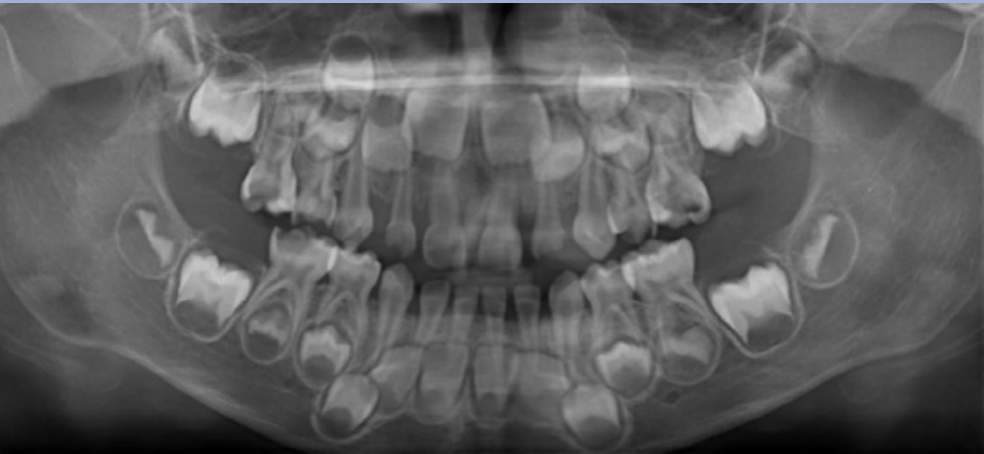

The age in this picture is characterized by the teeth erupted which are: Maxilla ABCDE and Mandible ABCDE. The teeth unerupted are the Maxilla 1234567 and the Second molar in the Maxilla- 1/3 Crown completed, Mandible- 1/3 crown completed